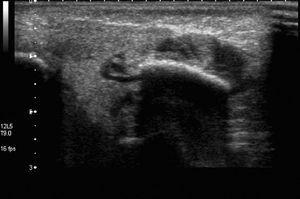

La ecografía objetivó aumento difuso de la glándula parótida, con presencia de nódulos hipoecoicos en su interior (fig. 1). En el estudio Doppler se visualizó aumento de la vascularización de la glándula. Serología de virus de la parotiditis (ELISA): IgG positiva, IgM negativa. Serología frente a virus de Epstein-Barr (VEB) y parvovirus: negativas. Estudio citoquímico de líquido cefalorraquídeo: normal. El urocultivo y el cultivo de líquido cefalorraquídeo fueron negativos. Se realizaron cultivo recto-vaginal y de leche materna que resultaron negativos. Se aisló S. agalactiae en el hemocultivo. Se inició tratamiento intravenoso con cefotaxima que se mantuvo durante 14 días.

Figura 1. Ecografía de la parótida derecha de la paciente 1, en la que se visualiza aumento difuso del tamaño de la glándula parótida.